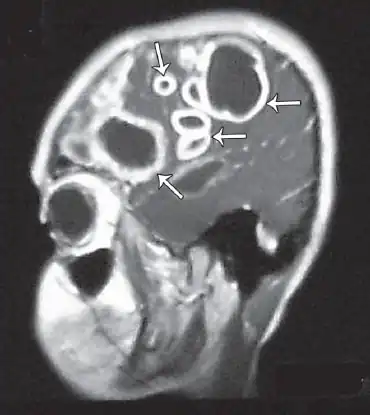

Cranial MRI revealed multiple, contrast-dense masses -abscesses

The diagnosis of Entamoeba histolytica in the brain abscesses is difficult for several reasons. Firstly, the aerobic and anaerobic cultures generally provide negative results.[9][10] In addition, the CT results are often inconclusive and even the parasitologic stool examinations and abdominal ultrasonography often yield normal results. However, direct examination of the abscess capsule may exhibit necrotic material, foamy histiocytes, rare eosinophills and ingested erythrocytes.[11] Spheric structures may insinuate the presence of Entamoeba histolytica trophozoites with Masson's trichrome stain. Additionally, PCR based analysis of the CSF can be used to positively identify the parasite in the system .[12] Combination of CT scans and PCR based identification along with the serological methods are the current diagnostic measures for detecting Entamoeba histolytica.